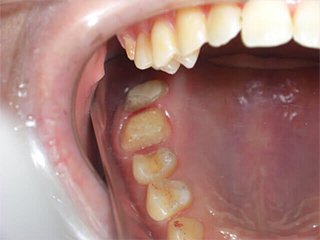

どこを治したかわかりますか?正解は、、、、、、、こうなってました。金属の詰め物、被せ物を取り、中の虫歯や金属片をきれいにし、形を整えたところです(写真は右上だけですが左上も同じようにします)。患者様が他院にて歯科治療を受け、健康保険適用の金属にて治療を終えてからもともとあったアトピー性皮膚炎が悪化し、調べたところ歯科金属アレルギーであったことが判明。当院にご相談に来られました。